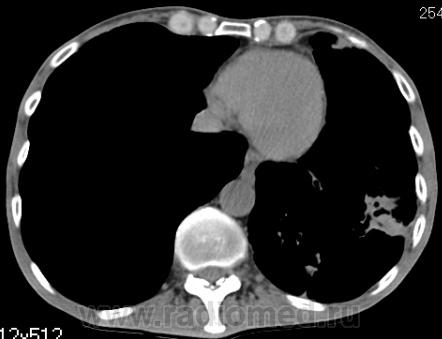

КТ - ОГК.  Ваше мнение коллеги?

На фоне консолидации полость без содержимого. Может быть всё что угодно, что сопровождается деструкцией. Нужны ещё томограммы в лёгочном окне.

Изображения выставлены все. Ваше мнение уважаемые коллеги?

Это КТ 2-летней давности и попало оно мне в руки, после недавнего прохождения контроля пациентом, когда мы стали перед вопросом о специфическом / не специфическом процессе.

Тогда, пациента 2 месяца лечили от пневмонии, лечили интенсивности, стационарно, в серьёзном учреждении.

Предположу аспергиллез

Почему? Признаки?